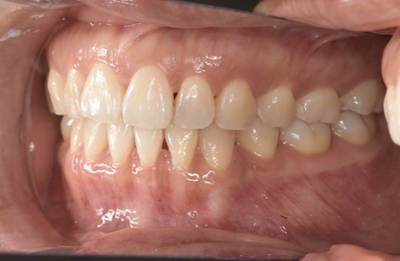

CASE 6

Before

After

基本情報

| 年齢・性別 | 35歳・男性 |

|---|---|

| 主訴 | 定期検診 |

| 治療内容 | スケーリング |

| 治療期間 | 30分 |

| 治療費 | 1,500円(保険診療) |

| リスク・副作用 | 知覚過敏、出血 |

| 治療方針 | まずは歯石除去を行い、ブラッシング方法の指導を行いました。炎症が落ち着いてきたら縁下歯石を除去して定期的なメンテナンスで歯石除去、着色除去を行います。 |

| 担当者所見 | 1年ぶりの歯医者。出血が多く炎症が強いため、歯石除去をしてご自身でもプラークコントロールができるようにブラッシングの方法をお伝えしました。 |